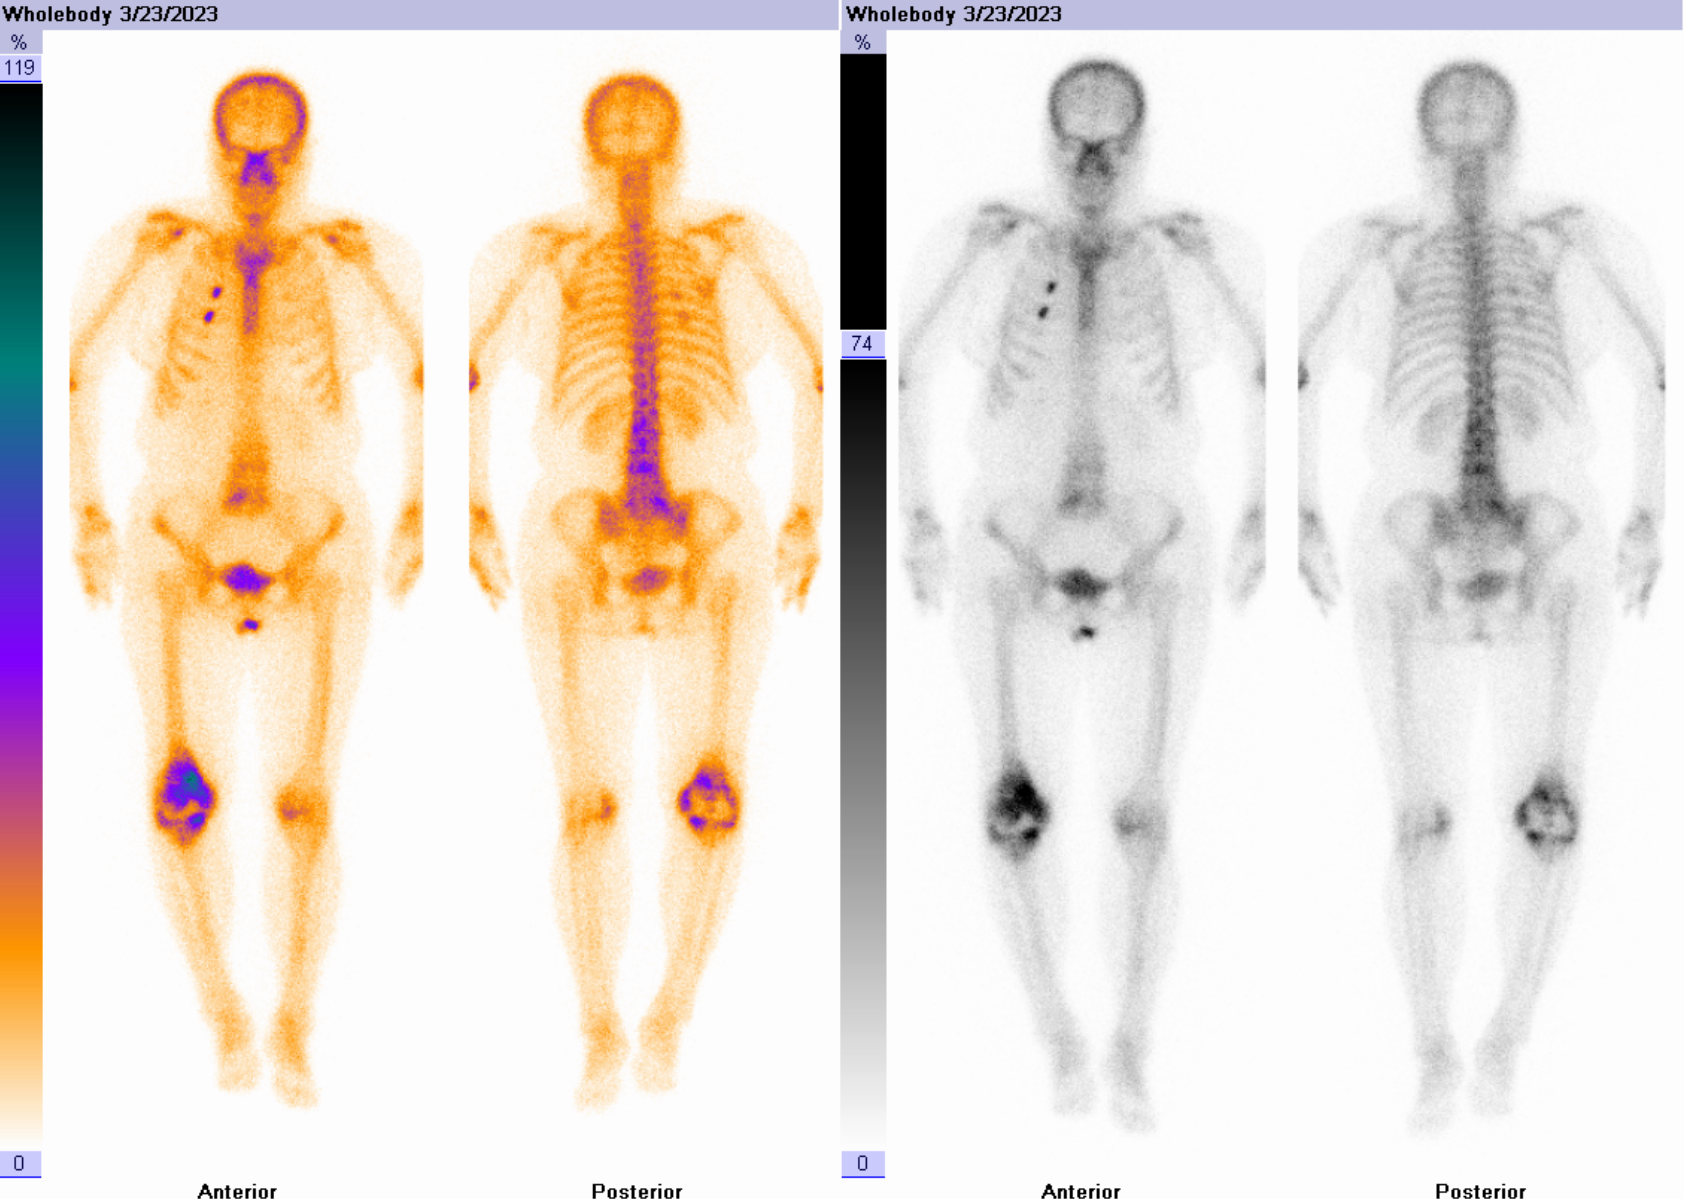

女性患者,8年前因“右侧膝关节炎”于我院行“右侧膝关节双间室置换”手术治疗,1年前无明显诱因出现右侧膝关节不适,自行口服止痛药物,不缓解。入院后完善相关化验检查,血常规:中性粒细胞计数7.69↑*10^9/L、C反应蛋白未见明显异常、血沉:37.0↑mm。

三相骨显像结果提示:右膝关节置换术后,三相骨显像血流相、血池相及延迟相阳性,结合影像特征考虑假体松动合并感染。

患者后续行手术治疗,术中见关节腔内脓液形成,膝关节假体松动。

①假体周围感染:典型表现为血流相、血池相、延迟相显像剂明显异常浓聚、范围广且弥漫,同机CT常可见软组织影、骨质破坏等影像。

②假体松动:典型表现为血流相、血池相在着力点附近出现放射性高摄取,延迟相可见假体两端局限性放射性浓聚,同机CT常可见骨吸收、骨质疏松等表现。